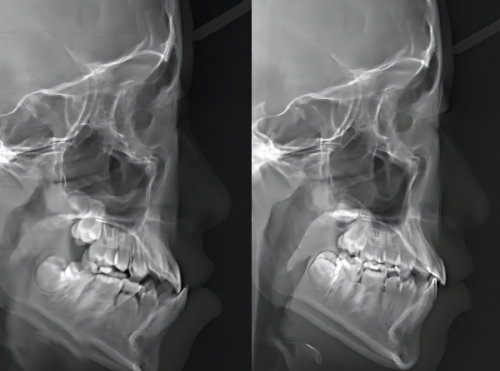

牙齿矫正患者:有患者因深覆合来矫正,医生根据情况制定方案,耐心解答疑问,全程一次性付费,无额外收费,历经近三年矫正,成效良好。